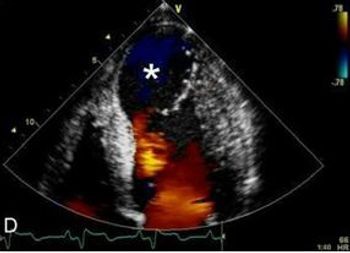

These presenting symptoms began after a near syncopal episode. The patient has no significant medical or surgical history. More details, here.